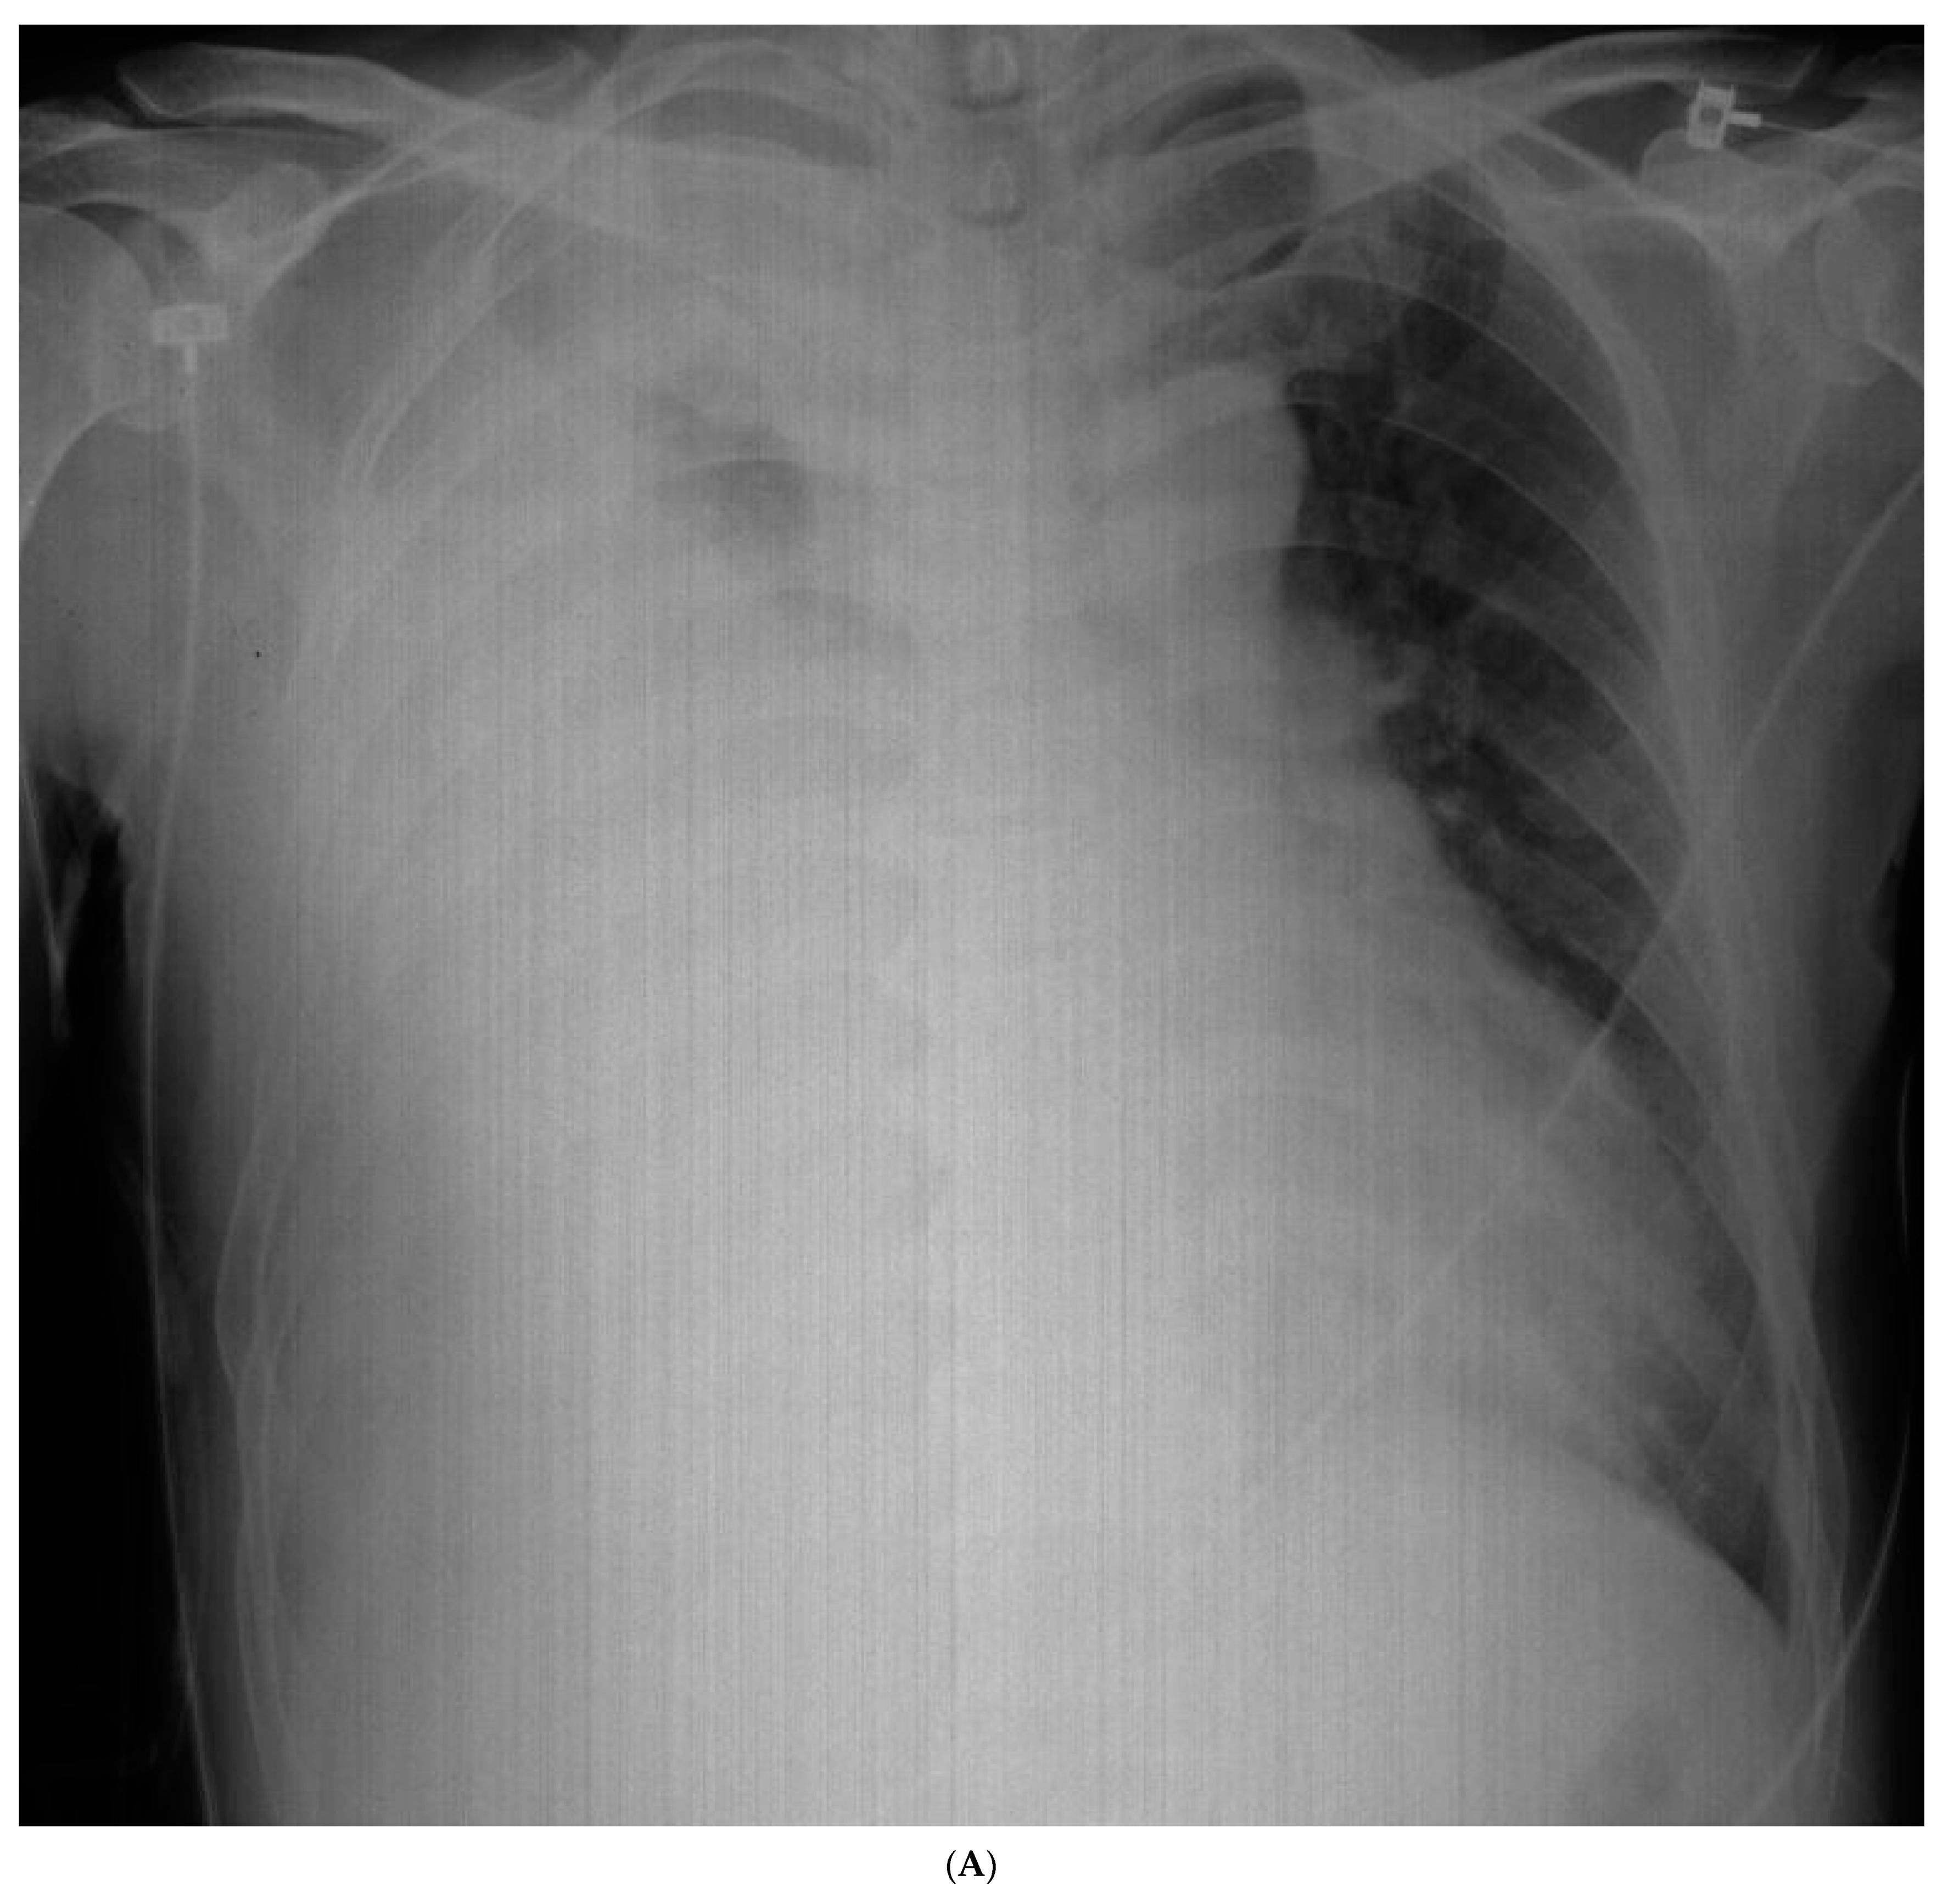

2. Case Report